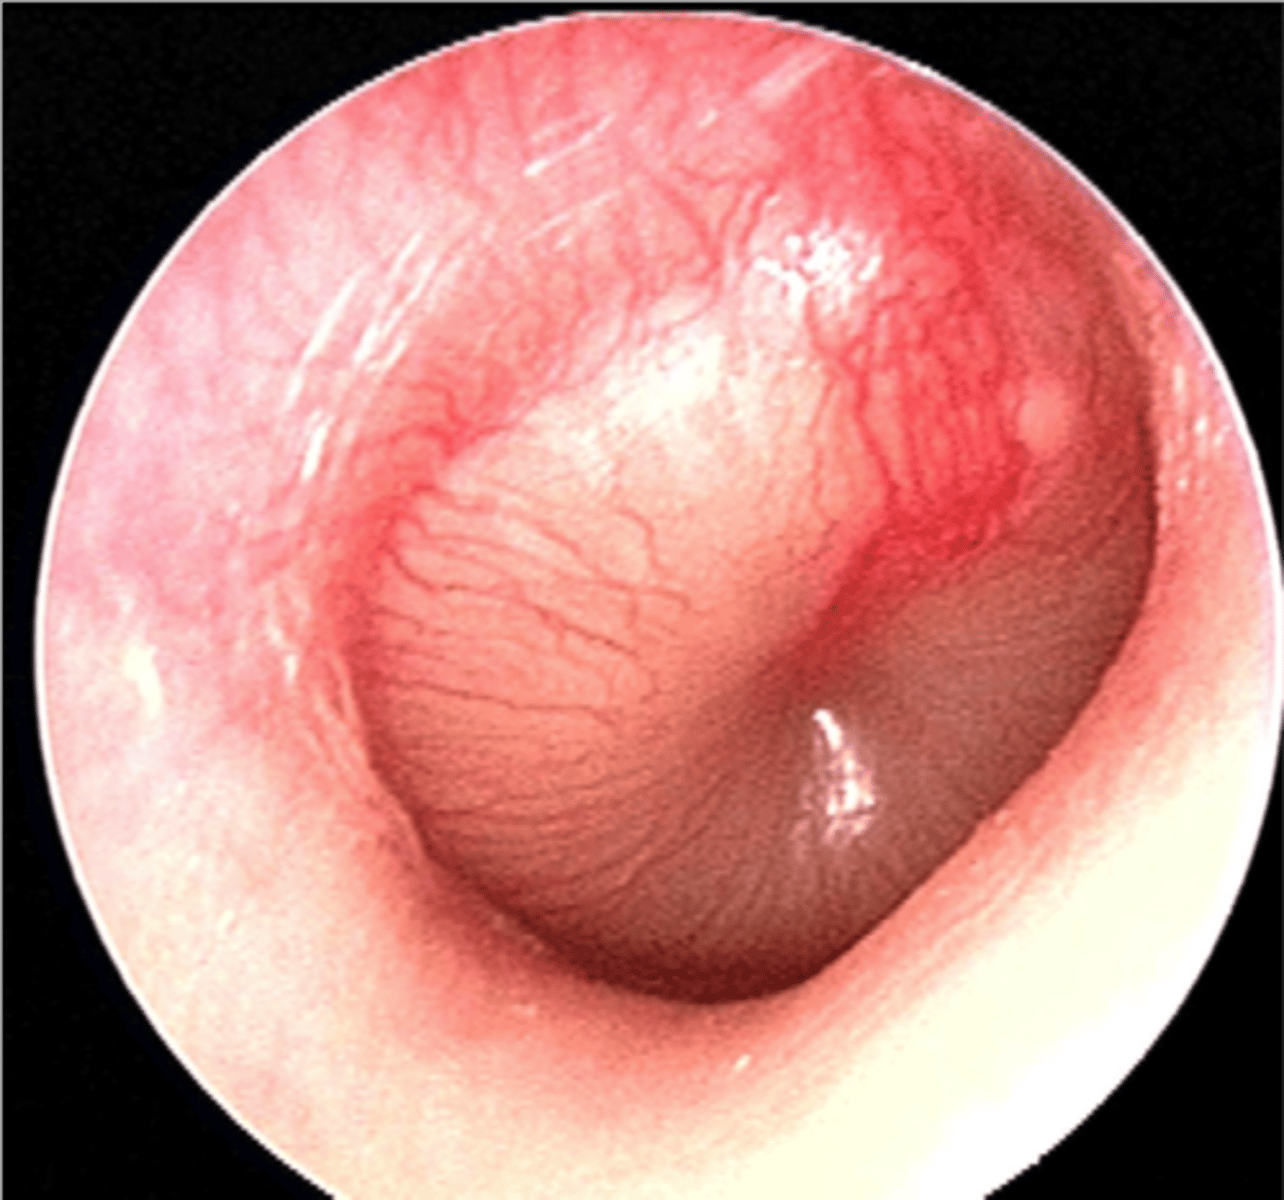

Acute otitis media

INFECTION of middle ear

TM bulging

Pain/pulling ear

Conductive HL dt purulent material

Erythema

<p>INFECTION of middle ear</p><p>TM bulging</p><p>Pain/pulling ear</p><p>Conductive HL dt purulent material</p><p>Erythema</p>